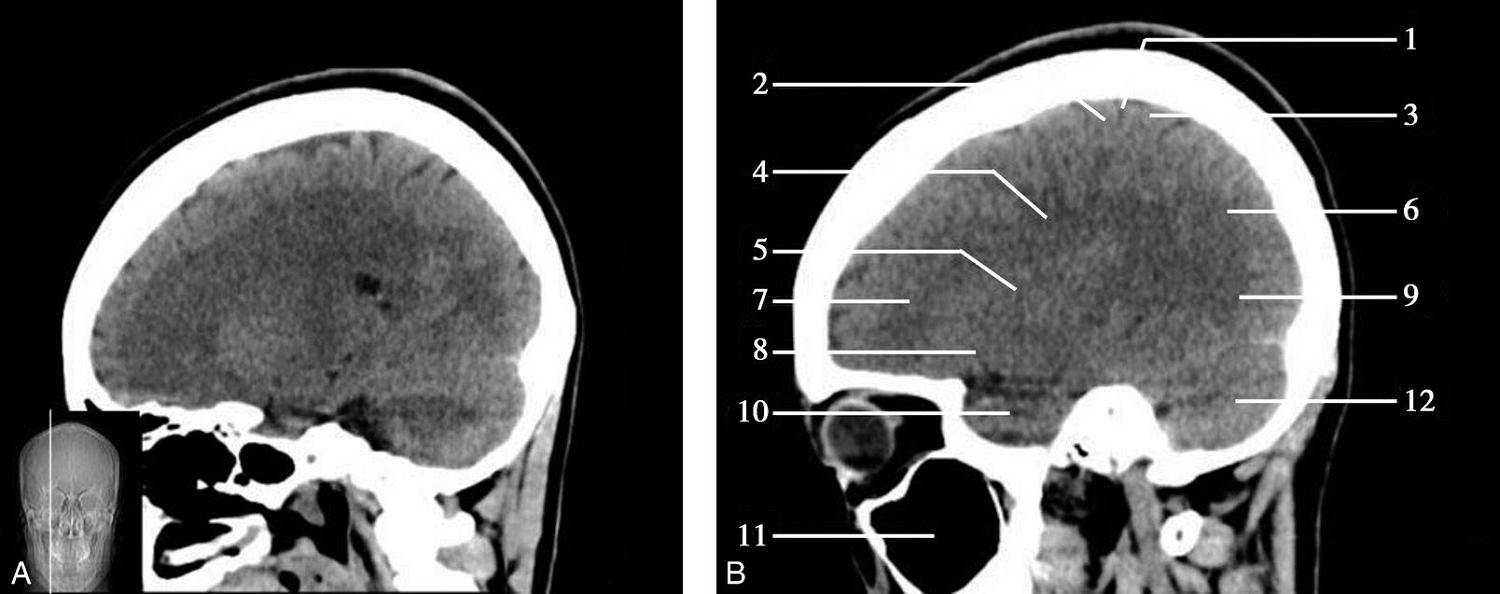

重要结构:尾状核头、豆状核、内囊、外囊、丘脑(图1-2-29~图1-2-31)。

图1-2-29 基底节层面

A.横断面;B.横断面标注

1.上矢状窦;2.大脑镰;3.额叶;4.扣带回;5.颞肌;6.胼胝体膝部;7.侧脑室前角;8.岛叶;9.尾状核头部;10.外囊;11.透明隔;12.中央沟;13.中央前回;14.中央后回;15.内囊前肢;16.内囊膝部;17.穹窿柱;18.豆状核;19.内囊后肢;20.丘脑;21.大脑内静脉;22.胼胝体压部;23.大脑大静脉;24.颞叶;25.脉络膜丛;26.顶叶;27.侧脑室三角区;28.顶枕沟;29.视辐射;30.枕叶;31.直窦

双侧侧脑室前角呈倒“八”字形向前外方伸展,其前壁为胼胝体膝部、内侧壁为透明隔、外侧壁为尾状核头。透明隔后方与穹窿柱相连,穹窿柱与两侧背侧丘脑前部间为室间孔,沟通双侧侧脑室及第三脑室。第三脑室居双侧背侧丘脑间,呈纵向走行的裂隙状。尾状核头与背侧丘脑的外侧为“> <”形的内囊,由前肢、膝及后肢三部分组成,内囊与额盖、顶盖之间,由内侧向外侧依次为豆状核、外囊、屏状核、最外囊、岛叶及外侧裂。枕叶与顶叶分界为顶枕沟,此沟在胼胝体压部层面显示最佳。胼胝体压部外侧有侧脑室三角区,内有脉络丛,常见钙化。大脑半球内侧面前部可见额内侧回和扣带回,后部可见扣带回和舌回。

顶枕沟位于胼胝体之后,是半球内侧面的一条较深的沟,此沟后方及大脑镰两侧为枕叶,为顶枕叶的分界标志。外侧裂池位于半球凸面的中点处,并向内、向后延伸,可作为额、颞叶的分界标志。此层面同时出现大脑半球的额、颞、顶、枕4个叶。

基底节为脑卒中的好发部位,与纹状动脉的解剖特点有关,深穿支动脉的破裂和栓塞可分别引起基底节区的出血和梗死(图1-2-32、图1-2-33)。